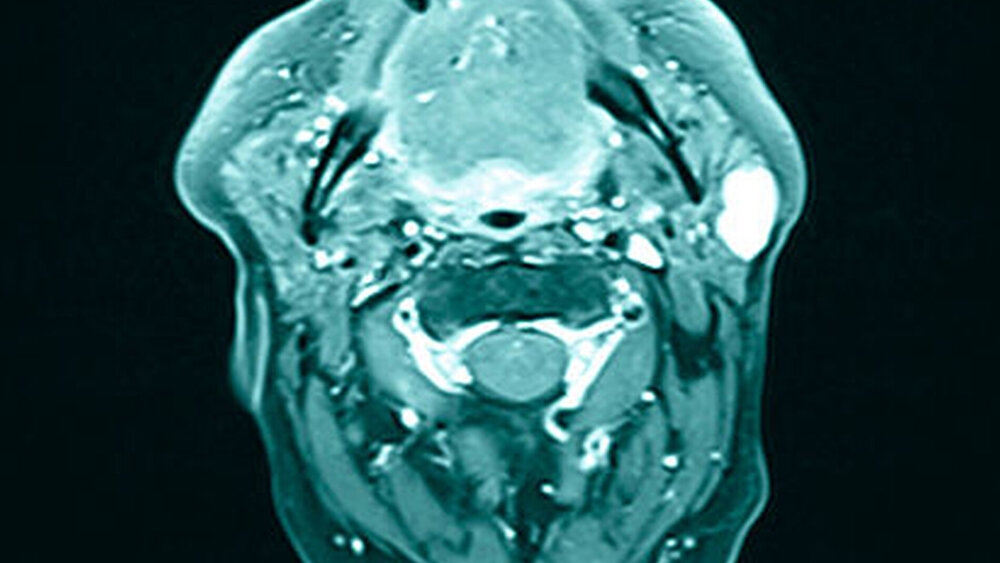

Zur weiteren Diagnostik erfolgte eine Sonografie (Abbildung 2) sowie eine drei- dimensionale Bildgebung mittels MRT (Abbildung 3). Hier zeigte sich eine Formation in der linken Glandula parotis ohne Infiltration der Nachbarstrukturen, die bildmorphologisch am ehesten einem pleomorphen Adenom entsprach.